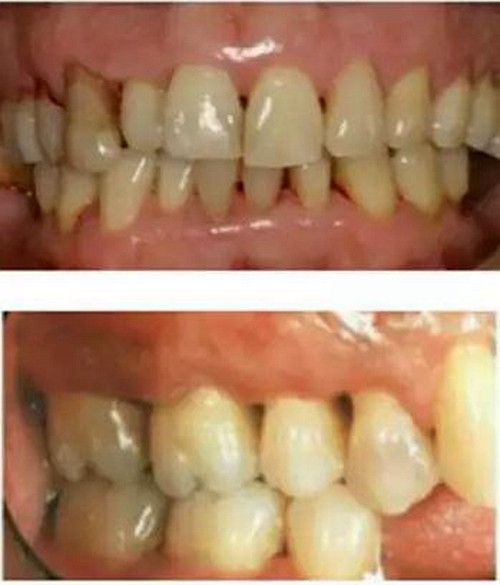

在猶疑之中,在未作任何牙周治療的情況下,牙齦出血可能突然減少或停止,很多患者慶幸自己的牙齦出血好了,其實是牙周病更加加重了,因為牙齦過度腫脹后,營養(yǎng)終于跟不上,導(dǎo)致了毛細(xì)血管的萎縮,因此會出現(xiàn)牙齦出血減少或停止的現(xiàn)象。但是同時牙槽骨也在喪失,于是,牙縫變稀變大(如上圖所示),更易殘留食物,口臭加重,牙根部分暴露,可能有冷熱刺激敏感。

1.牙周病矯正: 牙周病人前牙唇傾,間隙變大,可戴矯正器關(guān)閉間隙。